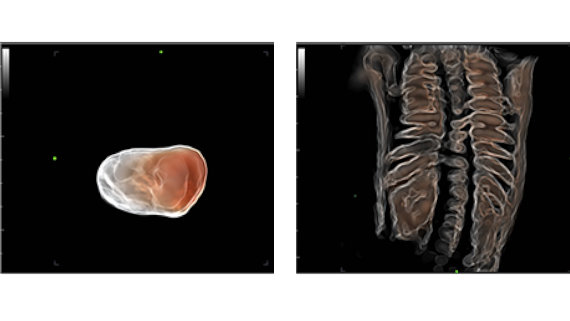

Smart Face proporciona una optimizaci├│n r├Īpida e inteligente del rostro del feto con una simple operaci├│n de un solo toque. Puede eliminar de forma inmediata las oclusiones (como el cord├│n umbilical, la placenta, el ├║tero y las extremidades) en los datos de volumen y excluir la informaci├│n de ruido no deseada, por lo que finalmente genera una visi├│n ├│ptima del rostro del feto con mayor simplicidad.

- Simplicidad con la optimizaci├│n autom├Ītica de im├Īgenes: Smart Face

- Smart Face proporciona una optimizaci├│n r├Īpida e inteligente del rostro del feto con una simple operaci├│n de un solo toque. Puede eliminar de forma inmediata las oclusiones (como el cord├│n umbilical, la placenta, el ├║tero y las extremidades) en los datos de volumen y excluir la informaci├│n de ruido no deseada, por lo que finalmente genera una visi├│n ├│ptima del rostro del feto con mayor simplicidad.